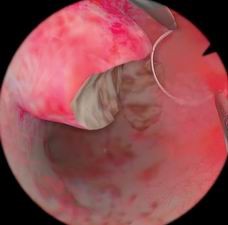

肌瘤切除模块

病例由易到难,简单的病例可发生在子宫底部,复杂的病例可发生在子宫前壁或者靠近输卵管口的地方

息肉切除模块